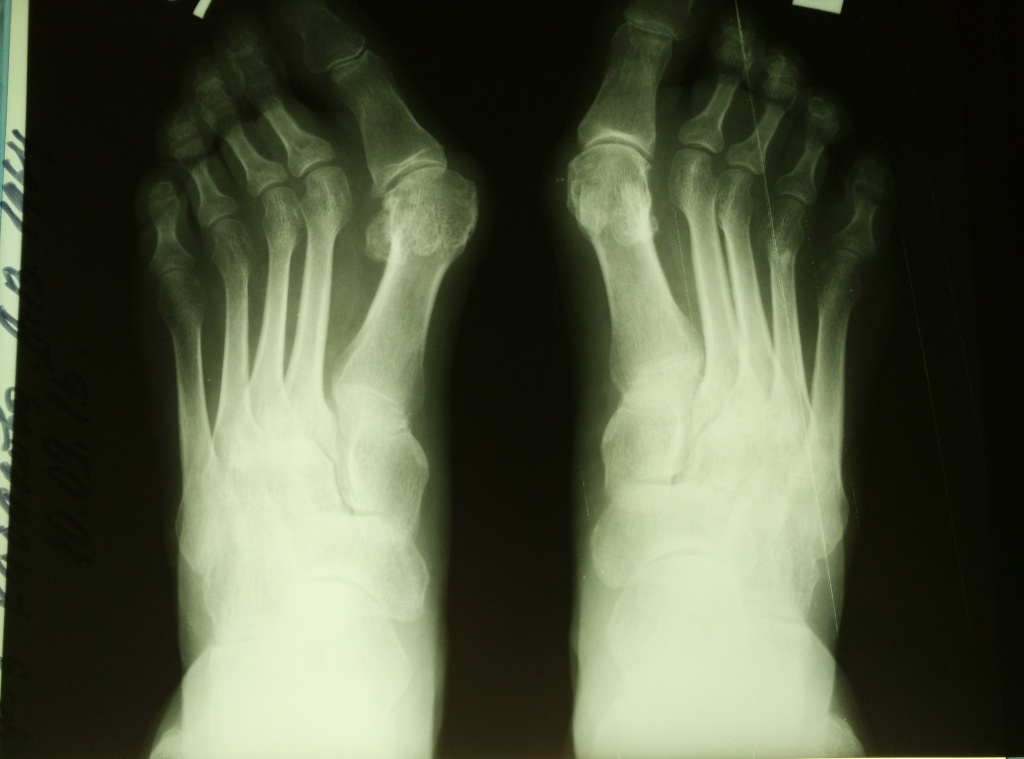

вид стопы пациентки и рентгенограммы до операции